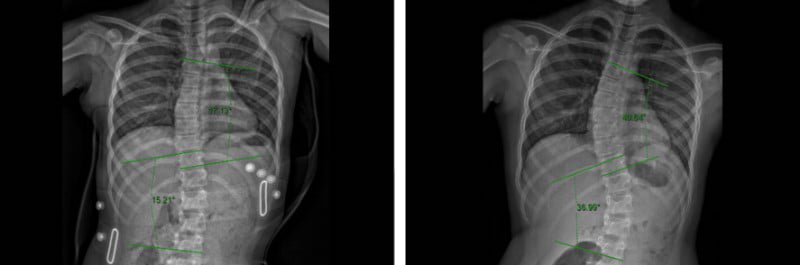

حتى أولئك الذين يعانون من اعوجاج العمود الفقري الشديد، حيث تزيد زاوية كوب عن 40 درجة، فقد استجابوا جيدًا لطريقه العلاج التي تعتمد على أحزمه الجنف تشينو-جينسينجن وبرنامج العلاج الطبيعي الذي يتبع مبادئ العلاج الطبيعي في شروث.

قبل و بعد

قبل و بعد